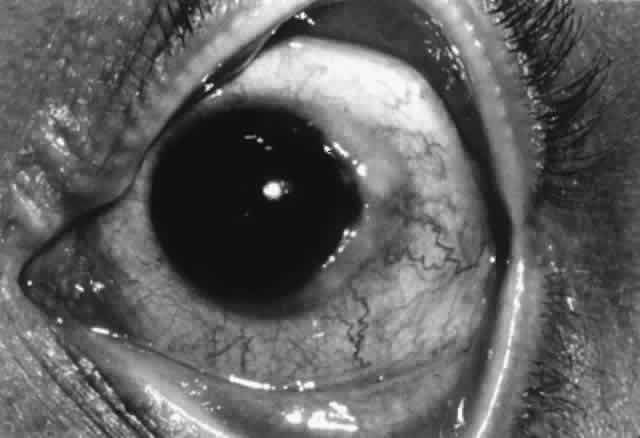

Pathogenesis

Several factors may be involved in pathogenesis. Mechanical irritation by the contact lens probably plays a role, especially lenses with thick edges, as seen in myopes. Accumulated deposits of protein, lipid, and minerals on the contact lens surface act as a source of antigens that can sensitize the conjunctiva. Chronic microtrauma by the lens and its deposits disrupts tight junctions between conjunctival epithelial cells, allowing allergens to penetrate. Damage to conjunctival epithelial cells induced by contact lenses and their deposits stimulates the production of neutrophil chemotactic factors, which play a role in the inflammatory response.83–85 Certain lens polymers (e.g., hydrogels) are more prone to accumulation of deposits. Also, larger lenses provide a greater surface area for deposits to accumulate and a greater surface area for antigens to contact the conjunctiva. Long wearing times allow a longer period of conjunctival exposure to antigen. Meibomian gland dysfunction may play a role in deposit formation and contact lens intolerance.86–88

The allergic mechanism in GPC is probably a basophil-rich delayed hypersensitivity (type IV) reaction with a possible IgE (type I) humoral component.82,89 An abnormal distribution of inflammatory cells is seen. There are mast cells in the conjunctival epithelium (not seen in normals) and increased numbers of mast cells in the substantia propria. Basophils and/or eosinophils, not usually seen in normal conjunctiva, may be found in increased numbers in both the epithelium and substantia propria.82 Although tear histamine levels are normal, tear immunoglobulins are increased.90,91 As with vernal, eosinophil major basic protein, which stimulates mast cell degranulation and possesses cytotoxic effects that may enhance the conjunctival inflammatory reaction, is found in increased amounts in the conjunctiva (but not in tears as in vernal) and undoubtedly plays a role.64 Tear tryptase levels in patients with GPC, a measure of mast cell degranulation, may provide an early marker for this disease.92

Treatment